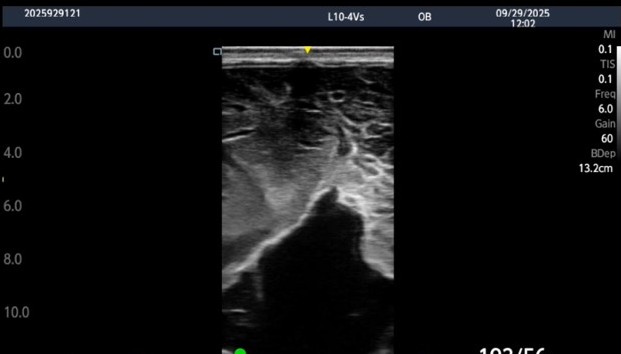

2025年10月3日 *********************************************************** 現場に到着すると、確かに母牛の右けん部あたりがボッコシ腫れています。 さらに皮膚の表面には引っ掻いたような跡も・・・。 これは挫傷(打撲傷)によって、皮下に血液や漿液などの液体が貯留している状態と診断しました。また「引っ掻いたような痕跡」から、他の牛が角でつついたり、乗駕などによるものでは?と考えました。もしかすると、この母牛は牛群の中で序列が低い、もしくは相性の悪い牛がいるのかもしれません。 そこで治療と並行し、牛の隔離もしくは少ない牛群への移動をお願いしました。これは「挫傷を治す」という目的もありますが、もう一つはストレスによる流産などのリスクを減らすためです。慢性的なストレスは、妊娠維持をするうえでNGです。 もしこういった牛を発見された際は、隔離もしくは移動をご検討ください。 |